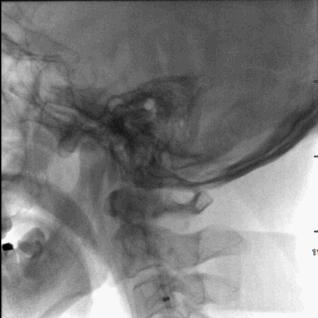

术前造影,BA近端闭塞。

术前造影,LC7次全闭塞。

术前造影,RICA 通过交通动脉向左侧颈内动脉及基底动脉尖代偿供血。